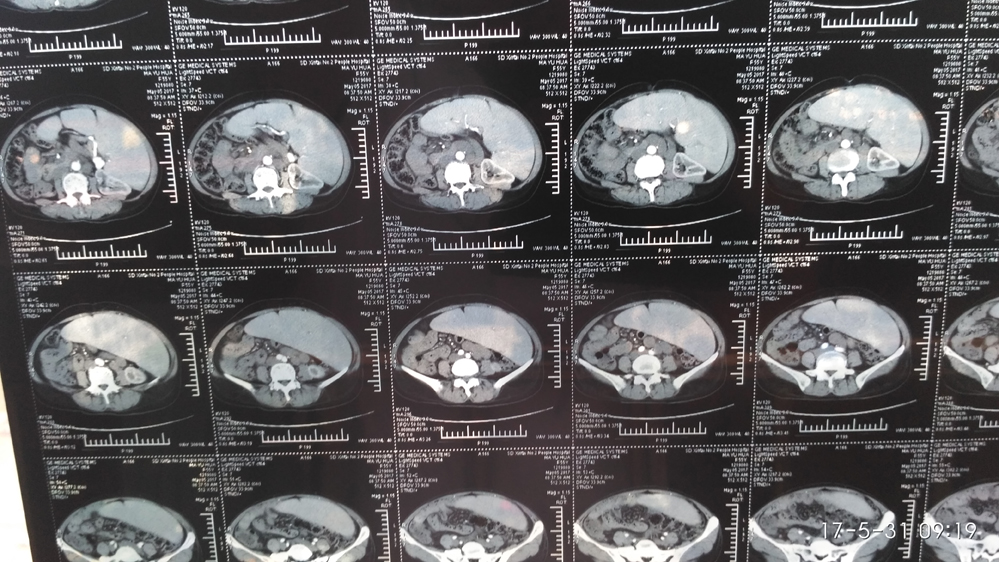

患者54岁,女性,于10余年前发现脾大,未做治疗。近期因腹部不适就诊于某医院,诊断为巨脾。血常规:WBC1.27×10/l,红细胞:3.20×10¹²/l,血小板:87×10/l,建议转省级医院手术切除。后患者没去上级医院而是选择来我院外一科住院手术。查体:腹部膨隆,脾明显增大,于右侧髂前上脊处触及脾下缘。脾长轴35cm,短轴15cm。CT:巨脾。于5月20日在全麻下行巨脾切除术。术中仔细的游离脾韧带,精细的结扎血管,经过3小时紧张的奋战,在出血不足50毫升的情况下成功切除巨脾。

据负责该手术的外一科主任陈立参介绍,巨脾为重度脾肿大,一般正常脾脏在左侧肋弓后,肋下触摸不到,当脾脏因为某种原因肿大超过脐右侧及或脐水平线以下称为巨脾。一般多见于黑热病、晚期血吸虫病、细菌或病毒感染、戈谢病、慢性粒细胞白血病,恶性淋巴瘤、骨髓纤维化等。治疗首选手术切除。手术因脾脏巨大,手术野暴露差,脾脏周围粘连重,脾脏供血多血管扩张明显,脾脏脆及血管壁薄易撕裂等原因,手术难度大、危险度高,手术中稍有不慎即可造成致命性大出血。此例巨脾切除手术的顺利完成,表明我院外科手术水平有了进一步提高。